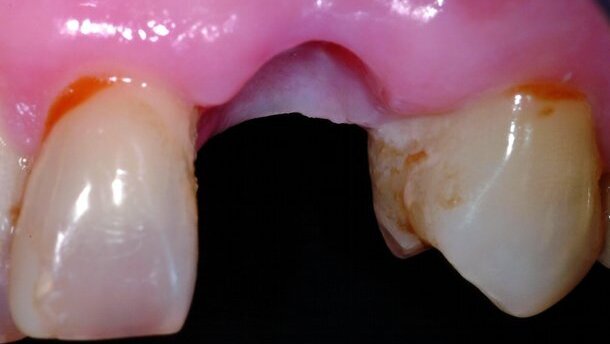

Cette patiente de 70 ans présente une canine supérieure avec une très grosse résorption externe (Figs. 1 et 2). L’étendue de la destruction ne permet pas un traitement conservateur et impose l’extraction. Nous sommes en présence d’une racine très longue sans perte osseuse et d’une patiente qui hésite un peu à accepter un traitement implantaire. Du fait de la longueur de racine qui risque de ne pas permettre une stabilité primaire suffisante, la technique de comblement d’alvéole après extraction est choisie. Cette technique permettra la conservation du volume dans le temps, en permettant également à la patiente de prendre sa décision.